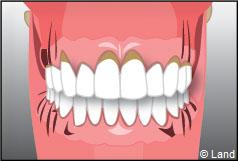

GENCIVE SAINE

PREMIERS SIGNES

LA GINGIVITE

LA PARODONTITE

L’os alvéolaire est touché et se détruit avec perte d’attache de la dent. La destruction va progresser pour devenir ensuite irréversible. Si rien n’est fait à temps, la mobilité dentaire va augmenter et conduire à la perte de la dent.